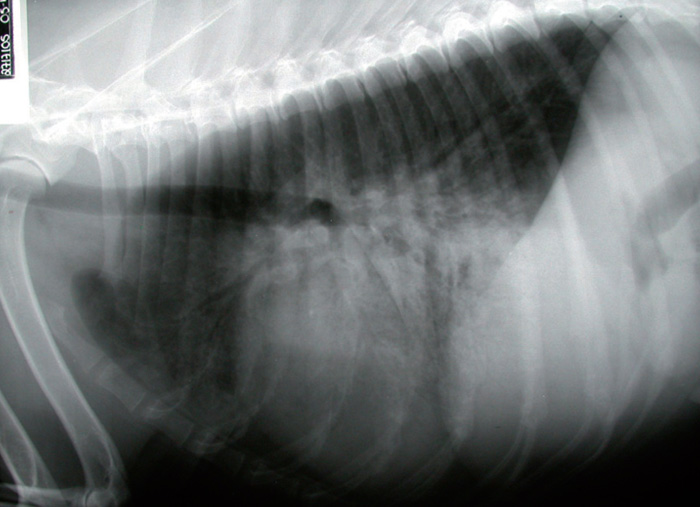

Image Congestive heart failure, dog, radiograph MSD Veterinary Manual Dog Congestive Heart Failure Meds Torsemide is most commonly used to treat refractory chf (stage d) when furosemide is no. congestive heart failure in dogs can be caused by several factors, including high blood pressure, congenital heart defects, heartworm. Your beloved pet can have heart problems just like you. heart failure and congestive heart failure are medical syndromes in which a dog exhibits. Dog Congestive Heart Failure Meds.